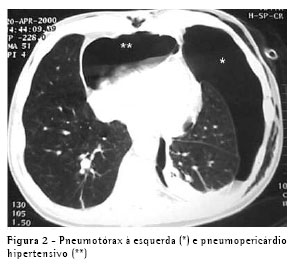

Um paciente do sexo masculino, com 40 anos, apresentando fibrilação atrial consultou um cardiologista. Ele não era tabagista e suas radiografias de tórax mostraram adenopatia hilar no lobo inferior direito. A tomografia computadorizada (TC) revelou uma massa central invadindo a veia pulmonar inferior e comprimindo o átrio esquerdo (Figura 1A). Uma lesão endobrônquica foi vista no brônquio lobar inferior direito e fez-se uma biopsia. Os resultados foram compatíveis com carcinoma neuroendócrino de grandes células. O paciente foi submetido a três ciclos de quimioterapia à base de cisplatina e a radioterapia. As TCs subseqüentes (Figura 1B) e exames broncoscópicos revelaram uma resposta altamente positiva ao tratamento Ele foi submetido a uma pneumonectomia direita radical incluindo uma porção do contorno do átrio esquerdo (primeira margem de ressecção positiva na altura da veia pulmonar inferior) e do pericárdio para-hilar. O defeito pericárdico foi enxertado com pericárdio bovino e um orifício de 2 cm foi deixado na linha de sutura para permitir que fluidos ou ar pudessem sair livremente do saco pericárdico. O paciente recebeu alta no quinto dia de um pós-operatório curto e sem intercorrências. Dez dias depois, ele retornou ao hospital apresentando hipotensão postural e dor subesternal constante. A radiografia de tórax mostrou pneumopericárdio (Figure 1C), confirmado na TC, que também revelou múltiplas bolsas de ar e nível ar-líquido no espaço pleural, sugerindo fístula bronco-pleural (Figura 1D). Ele foi internado no hospital, um tubo torácico (36Fr) foi inserido no espaço pleural direito, e a broncoscopia mostrou uma pequenina (1.0 mm) fístula no coto brônquico. Não havia sinais ou sintomas de infecção e o líquido pleural estava claro, com menos do que 300 células, das quais 80% eram eosinófilos. O paciente não apresentou fuga aérea intra-operatória ou pós-operatória através do tubo torácico. Os antibióticos foram dados, e a evolução foi excelente. O tubo torácico foi retirado no décimo dia pós-operatório. O pneumopericárdio sintomático desapareceu imediatamente após uma drenagem pleural e não houve nenhum empiema ou outras complicações.

O problema foi resolvido, e os cateteres foram removidos. No dia seguinte, o paciente apresentou hipotensão, taquicardia e dispnéia. Por motives técnicos, não foi possível realizar um ecocardiograma. A TC mostrou um pneumotórax anterior esquerdo e um pneumopericárdio grande (Figura 2). Um tubo torácico 32 Fr foi inserido na cavidade pleural esquerda, e o problema foi totalmente resolvido. O paciente também foi submetido a uma pleurodese com talco em suspensão. A mesma solução simples (drenagem pleural) foi usada neste segundo caso.